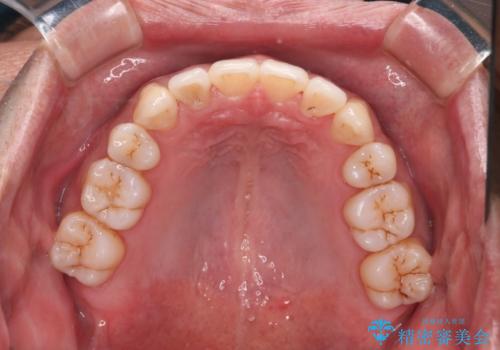

- 治療計画

叢生量が大きいため、上下顎両側4番を抜歯しました。矯正治療による歯肉退縮の著しい悪化もなく、主訴であるガタつきも改善できました。